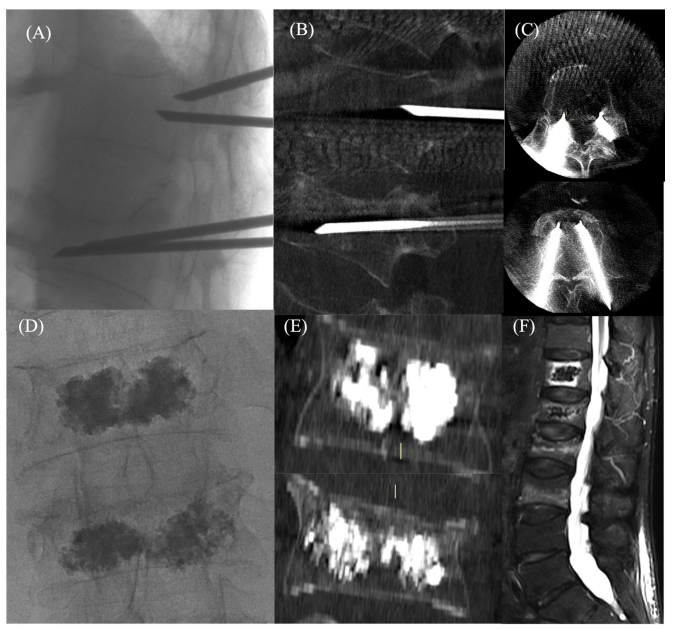

(图来自https://doi.org/10.3390/osteology2040017)

上图AI解读:70岁女性,骨质疏松症伴自发性T12和L1椎体压缩性骨折。

图片内容(从左到右,从上到下):

(A) 经皮、透视引导、双侧入路,显示进入D12和L1椎体压缩性骨折的通道和弯曲的针。这张图展示了手术过程中的一个步骤。医生通过透视(X光)引导,使用两根针(双侧入路)从背部穿刺进入患者的第12胸椎(T12)和第1腰椎(L1)。针是弯曲的,这样可以更好地贴合椎体的形状。

(B) 矢状面 和 (C) 轴向锥形束CT图像,显示针的正确位置。这两张图是锥形束CT扫描图像。(B) 是从侧面观察脊柱(矢状面),(C) 是从上往下观察脊柱(轴向)。这两张图用于确认针的位置是否准确,确保针尖位于椎体内正确的位置,为后续的骨水泥注入做准备。

(D) 椎体成形术后的前后位透视图像 和 (E) 冠状面锥形束CT图像显示均匀的骨水泥分布。这两张图展示了骨水泥注入后的效果。(D) 是从正面观察脊柱(前后位),(E) 是从正面观察脊柱(冠状面)。可以看到白色的骨水泥已经均匀地填充在椎体内,起到了支撑和稳定的作用。

(F) 一个月后的矢状位MRI STIR图像,显示椎体内骨髓水肿减轻。这张图是核磁共振(MRI)图像,用于观察骨折愈合的情况。STIR是一种特殊的MRI序列,对水肿非常敏感。图像显示,与手术前相比,椎体内的水肿(白色区域)明显减少,说明骨折正在愈合。